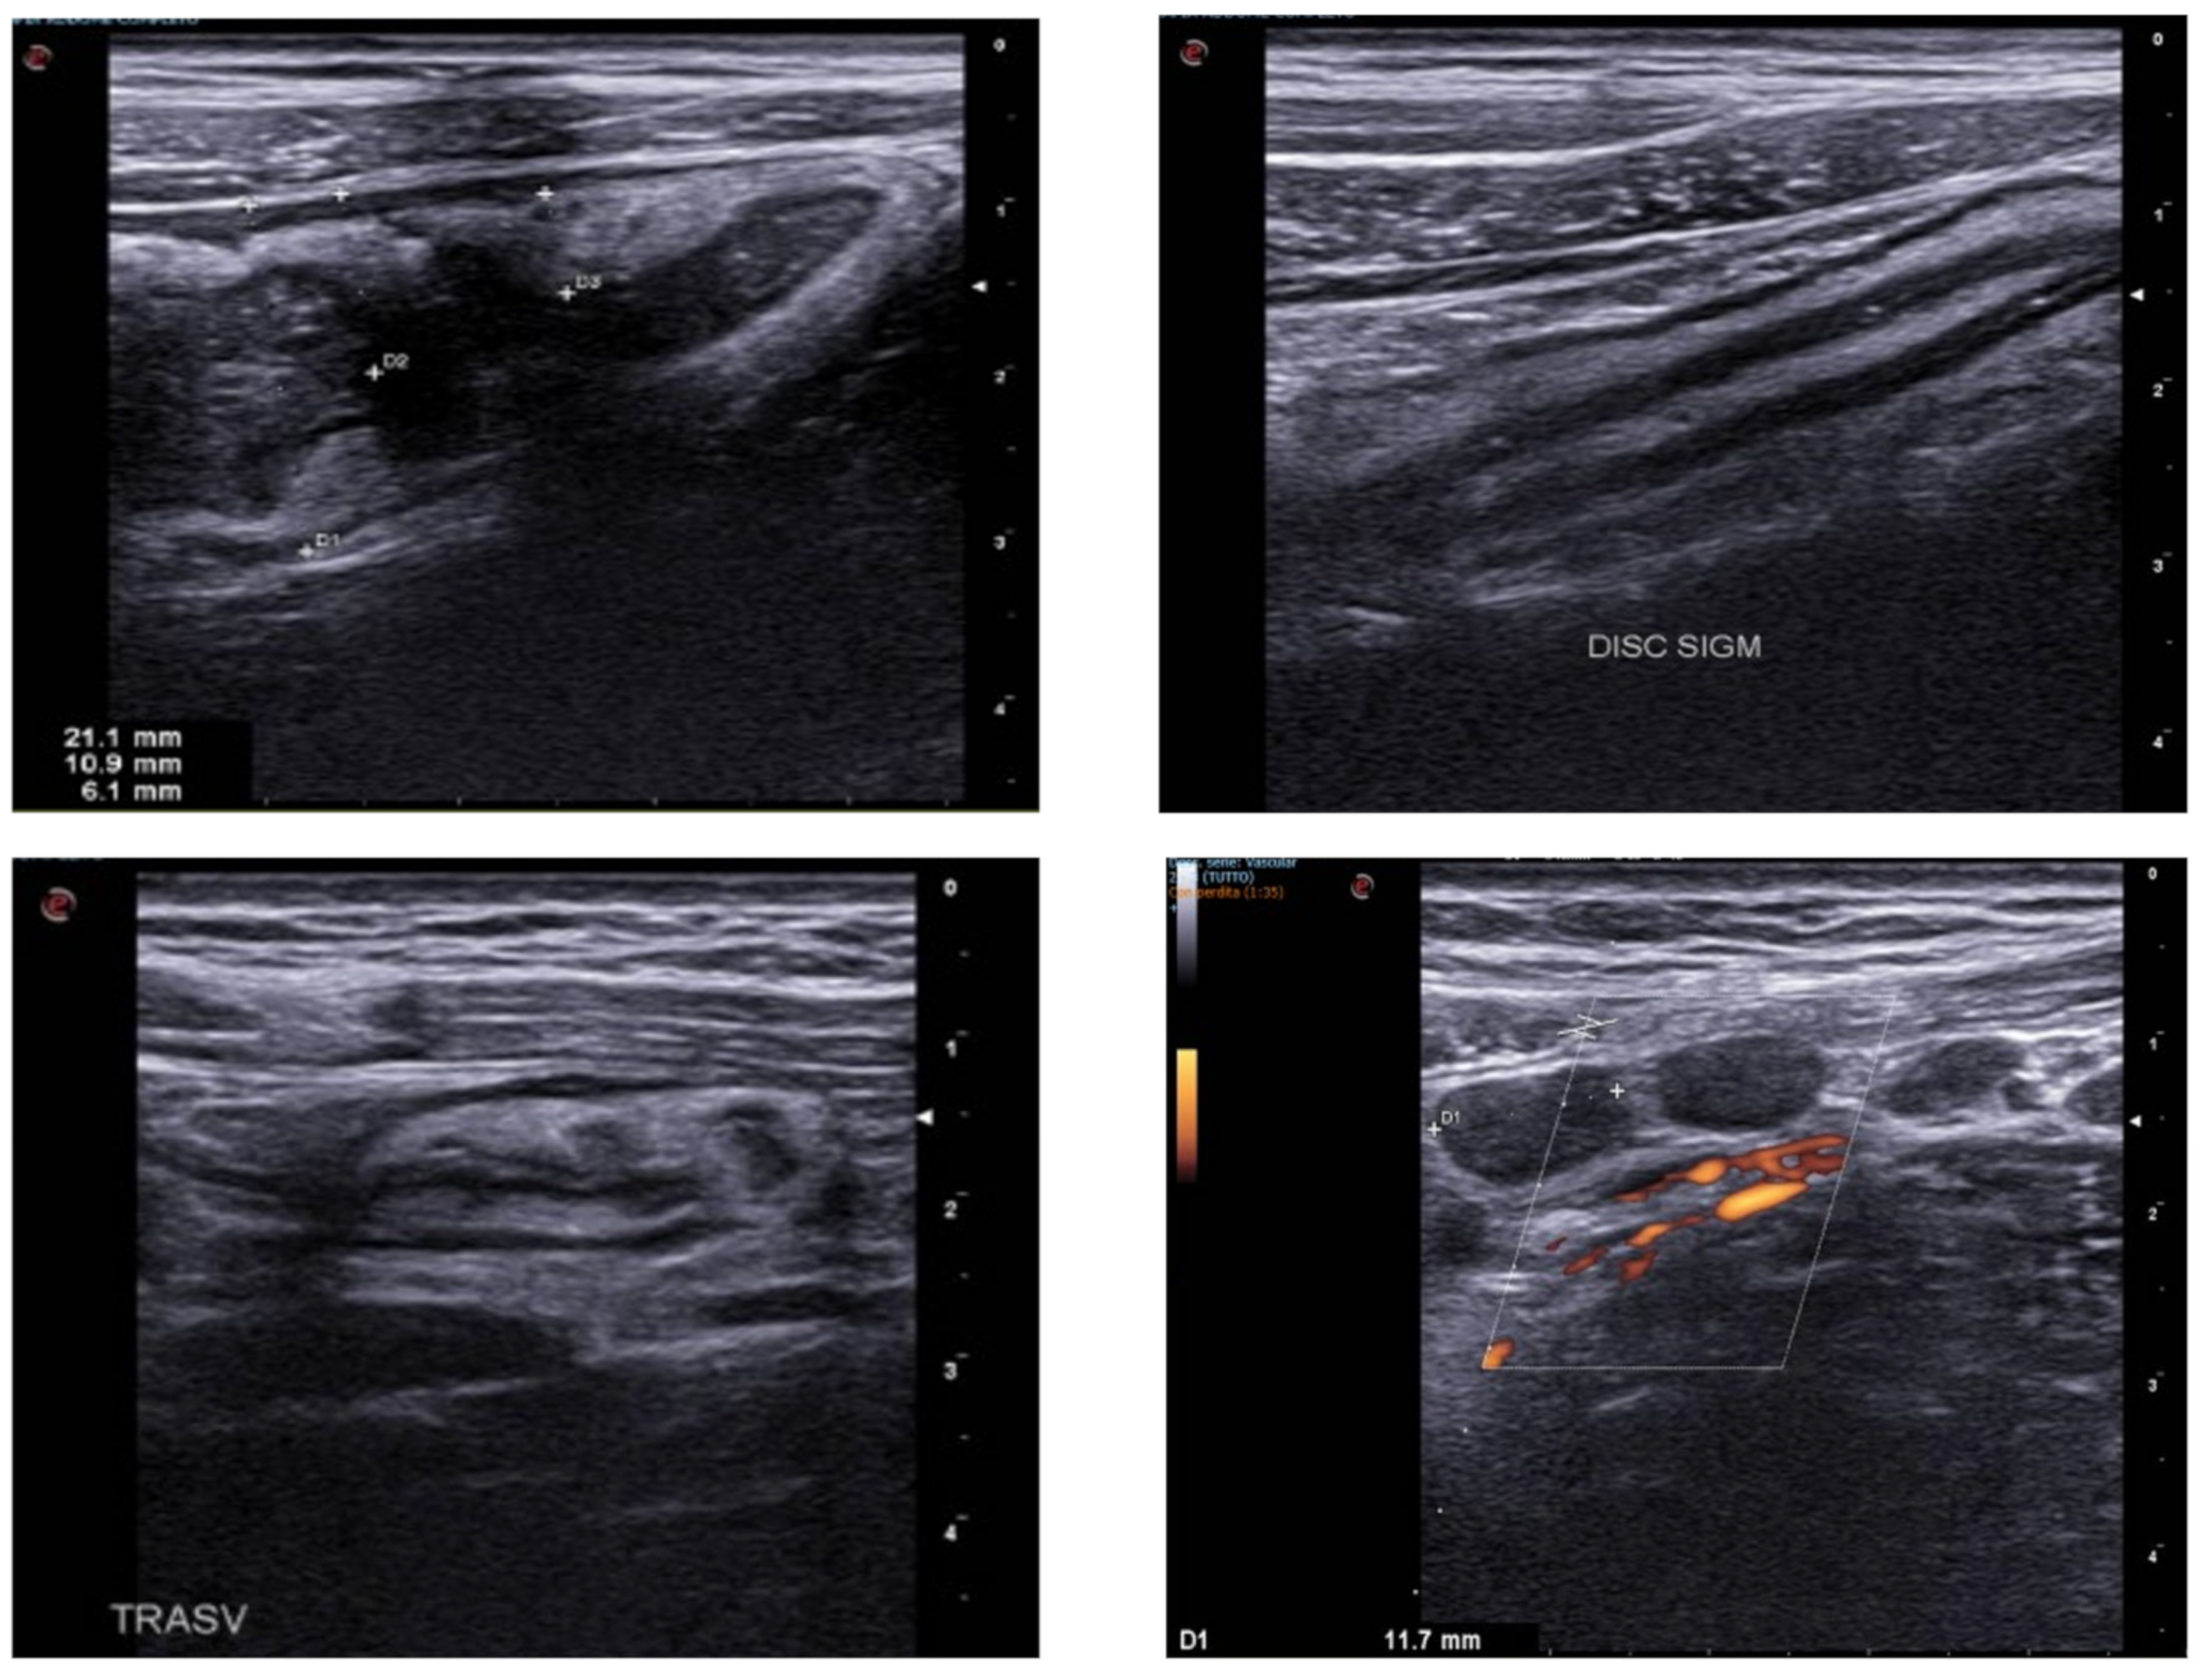

4. Acute Appendicitis

5. Acute Diverticulitis